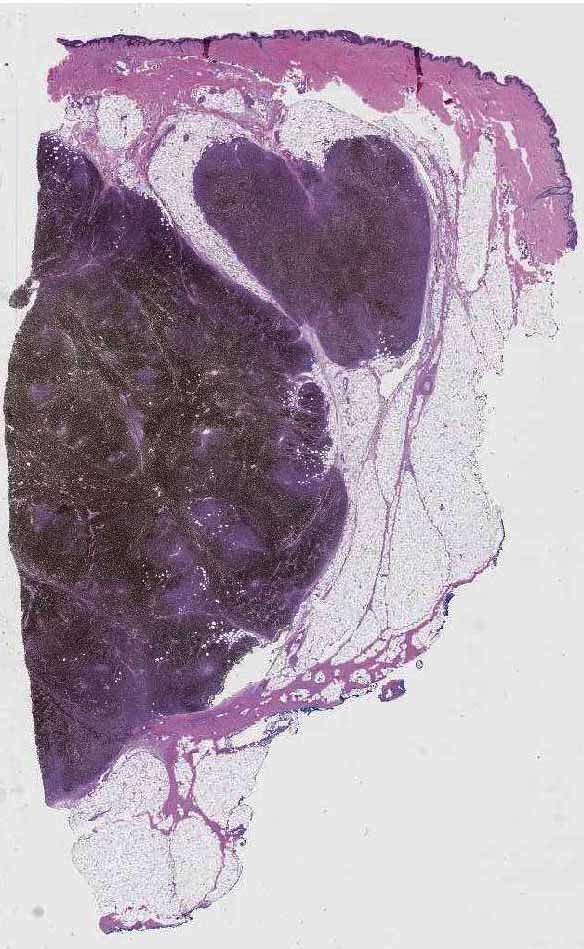

From www.pathologyoutlines.com

Pathology Outlines Vulvar melanoma Melanoma Vulva Vulval melanoma is the second most common type of vulval cancer. While the mortality rate of cutaneous melanoma. The most common symptom of vaginal or vulvar melanoma is unexpected bleeding from the area, (bleeding that occurs between periods or after the menopause). Melanoma of the vulva is a type of mucosal melanoma, which Vulvar melanoma is a type of skin. Melanoma Vulva.

Pathology Outlines Melanoma Melanoma Vulva Melanoma of the vulva is a type of mucosal melanoma, which Vulvar melanoma is a type of skin cancer that affects the surface area of the vagina. Fortunately, most of these are benign but 1% of all melanomas in women affect the vulva. The most common symptom of vaginal or vulvar melanoma is unexpected bleeding from the area, (bleeding that. Melanoma Vulva.